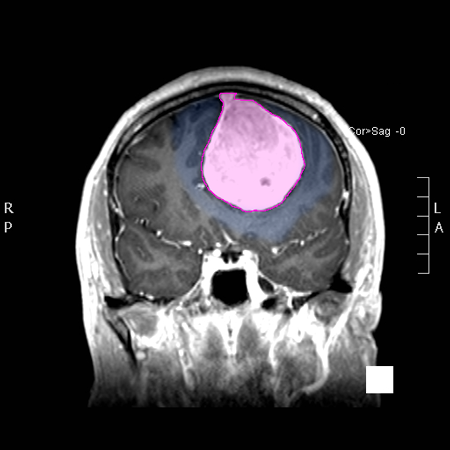

Τα μηνιγγιώματα του εγκεφάλου είναι οι πιο συχνά διαγνωσκόμενοι πρωτοπαθείς όγκοι της κρανιακής κοιλότητας. Εκφύονται από τις μήνιγγες, τα ινώδη περιβλήματα, του εγκεφάλου και είναι, στο μεγαλύτερο ποσοστό τους, καλοήθεις με αργή ανάπτυξη. Ανάλογα με τη θέση και το μέγεθος τους μπορεί να προκαλέσουν διάφορα συμπτώματα όπως επιληπτικές κρίσεις, αδυναμία ή/και υπαισθησία (μούδιασμα) σε ένα ή περισσότερα άκρα, διαταραχές του λόγου ή της όρασης, κ.α. Όχι σπάνια ανακαλύπτονται τυχαία σε απεικονιστικούς ελέγχους μη έχοντας προλάβει να δημιουργήσουν συμπτώματα. Η θεραπεία τους, όταν προκαλούν ή ενδέχεται να προκαλέσουν συμπτώματα είναι χειρουργική, ακτινοχειρουργική ή, σπανιότερα, ακτινοθεραπευτική. |

Επίπτωση και Αιτίες Τα μηνιγγιώματα του εγκεφάλου αποτελούν το 34% των ετησίως διαγνωσκόμενων πρωτοπαθών όγκων του εγκεφάλου και προσβάλλουν συχνότερα τις γυναίκες (η αναλογία προς τους άντρες είναι περίπου 2 έως 3:1). Ανακαλύπτονται πιο συχνά σε ηλικίες ανάμεσα στα 40-70 έτη. Το 90% από αυτά είναι καλοήθη, και μεγαλώνουν αργά, με ρυθμό συνήθως μερικών χιλιοστών ανά έτος, το 8% θεωρούνται άτυπα και έχουν μεγαλύτερο ρυθμό ανάπτυξης, και το 2% παρουσιάζουν κακοήθη χαρακτηριστικά. Για την δημιουργία των μηνιγγιωμάτων έχει αποδειχθεί, σε διαφόρους βαθμούς, ότι ενέχονται: παλαιότερη έκθεση σε ιονισμένη ακτινοβολία (όπως π.χ. ακτινοθεραπεία εγκεφάλου), ορμονολογικοί παράγοντες (κάποια μηνιγγιώματα φέρουν υποδοχείς οιστρογόνων, προγεστερόνης και ανδρογόνων) και γενετικοί παράγοντες (αυξημένη επίπτωση σε ασθενείς με π.χ. νευροϊνωμάτωση). Στα περισσότερα μηνιγγιώματα η αιτία της δημιουργίας τους δεν μπορεί να απομονωθεί ή να αποδειχθεί, όπως συμβαίνει με τους περισσότερους καλοήθεις όγκους. |

Συμπτώματα Τα συμπτώματα των μηνιγγιωμάτων ορίζονται από τον συνδυασμό της θέσης και του μεγέθους τους. Μικρά μηνιγγιώματα σε επαφή και με πίεση επί ευγενών περιοχών του εγκεφάλου, όπως αυτές που ελέγχουν την κίνηση, τον λόγο ή την όραση μπορεί να προκαλέσουν περισσότερα συμπτώματα από πολύ μεγαλύτερα σε μέγεθος μηνιγγιώματα που πιέζουν λιγότερο σημαντικές περιοχές. Τα συχνότερα συμπτώματα είναι οι επιληπτικές κρίσεις, η αδυναμία ή/και η υπαισθησία (μούδιασμα) σε ένα ή περισσότερα άκρα και οι διαταραχές του λόγου και της όρασης. Όπως προαναφέρθηκε τα μηνιγγιώματα μπορεί να ανακαλυφθούν τυχαία σε απεικονιστικό έλεγχο του εγκεφάλου για διαφορετικούς λόγους, χωρίς να έχουν προκαλέσει (ακόμη) κανένα σύμπτωμα |

Διάγνωση Απαραίτητα είναι: Η λεπτομερής λήψη ιστορικού και η κλινική εξέταση, Η μαγνητική τομογραφία του εγκεφάλου με σκιαγραφικό, Σε ορισμένες περιπτώσεις: Η μαγνητική αγγειογραφία ή/και φλεβογραφία του εγκεφάλου, Η μαγνητική τομογραφία του εγκεφάλου με σκιαγραφικό για νευροπλοήγηση, Ηλεκτροεγκεφαλογράφημα και άλλες εξειδικευμένες εξετάσεις όπως μέτρηση οπτικής οξύτητας και οπτικών πεδίων προτείνονται κατά περίπτωση. |